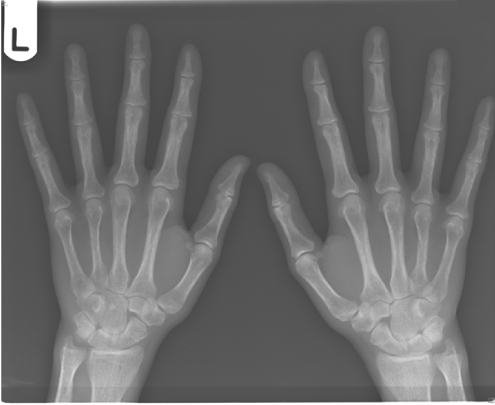

Subperiosteal bone erosion of proximal phalanges and metacarpals in hyperparathyroidism

Primary hyperparathyroidism (pHPT) is the inappropriate excess production of parathyroid hormone. The term hyperparathyroidism was first coined in the 1920s to describe a syndrome characterised by bone disease, renal stones, fatigue, hypercalcaemia and high urine calcium. The diagnosis was dependent on symptoms related to “bones, stones, abdominal groans and moans” which often correlated with severe bone disease, advanced kidney disease, psychiatric and neuromuscular disorders respectively. The symptoms were often associated with evidence of calcification of the kidneys, bone erosion of the fingers, boney tumours and changes in the appearance of the skull on Xray.